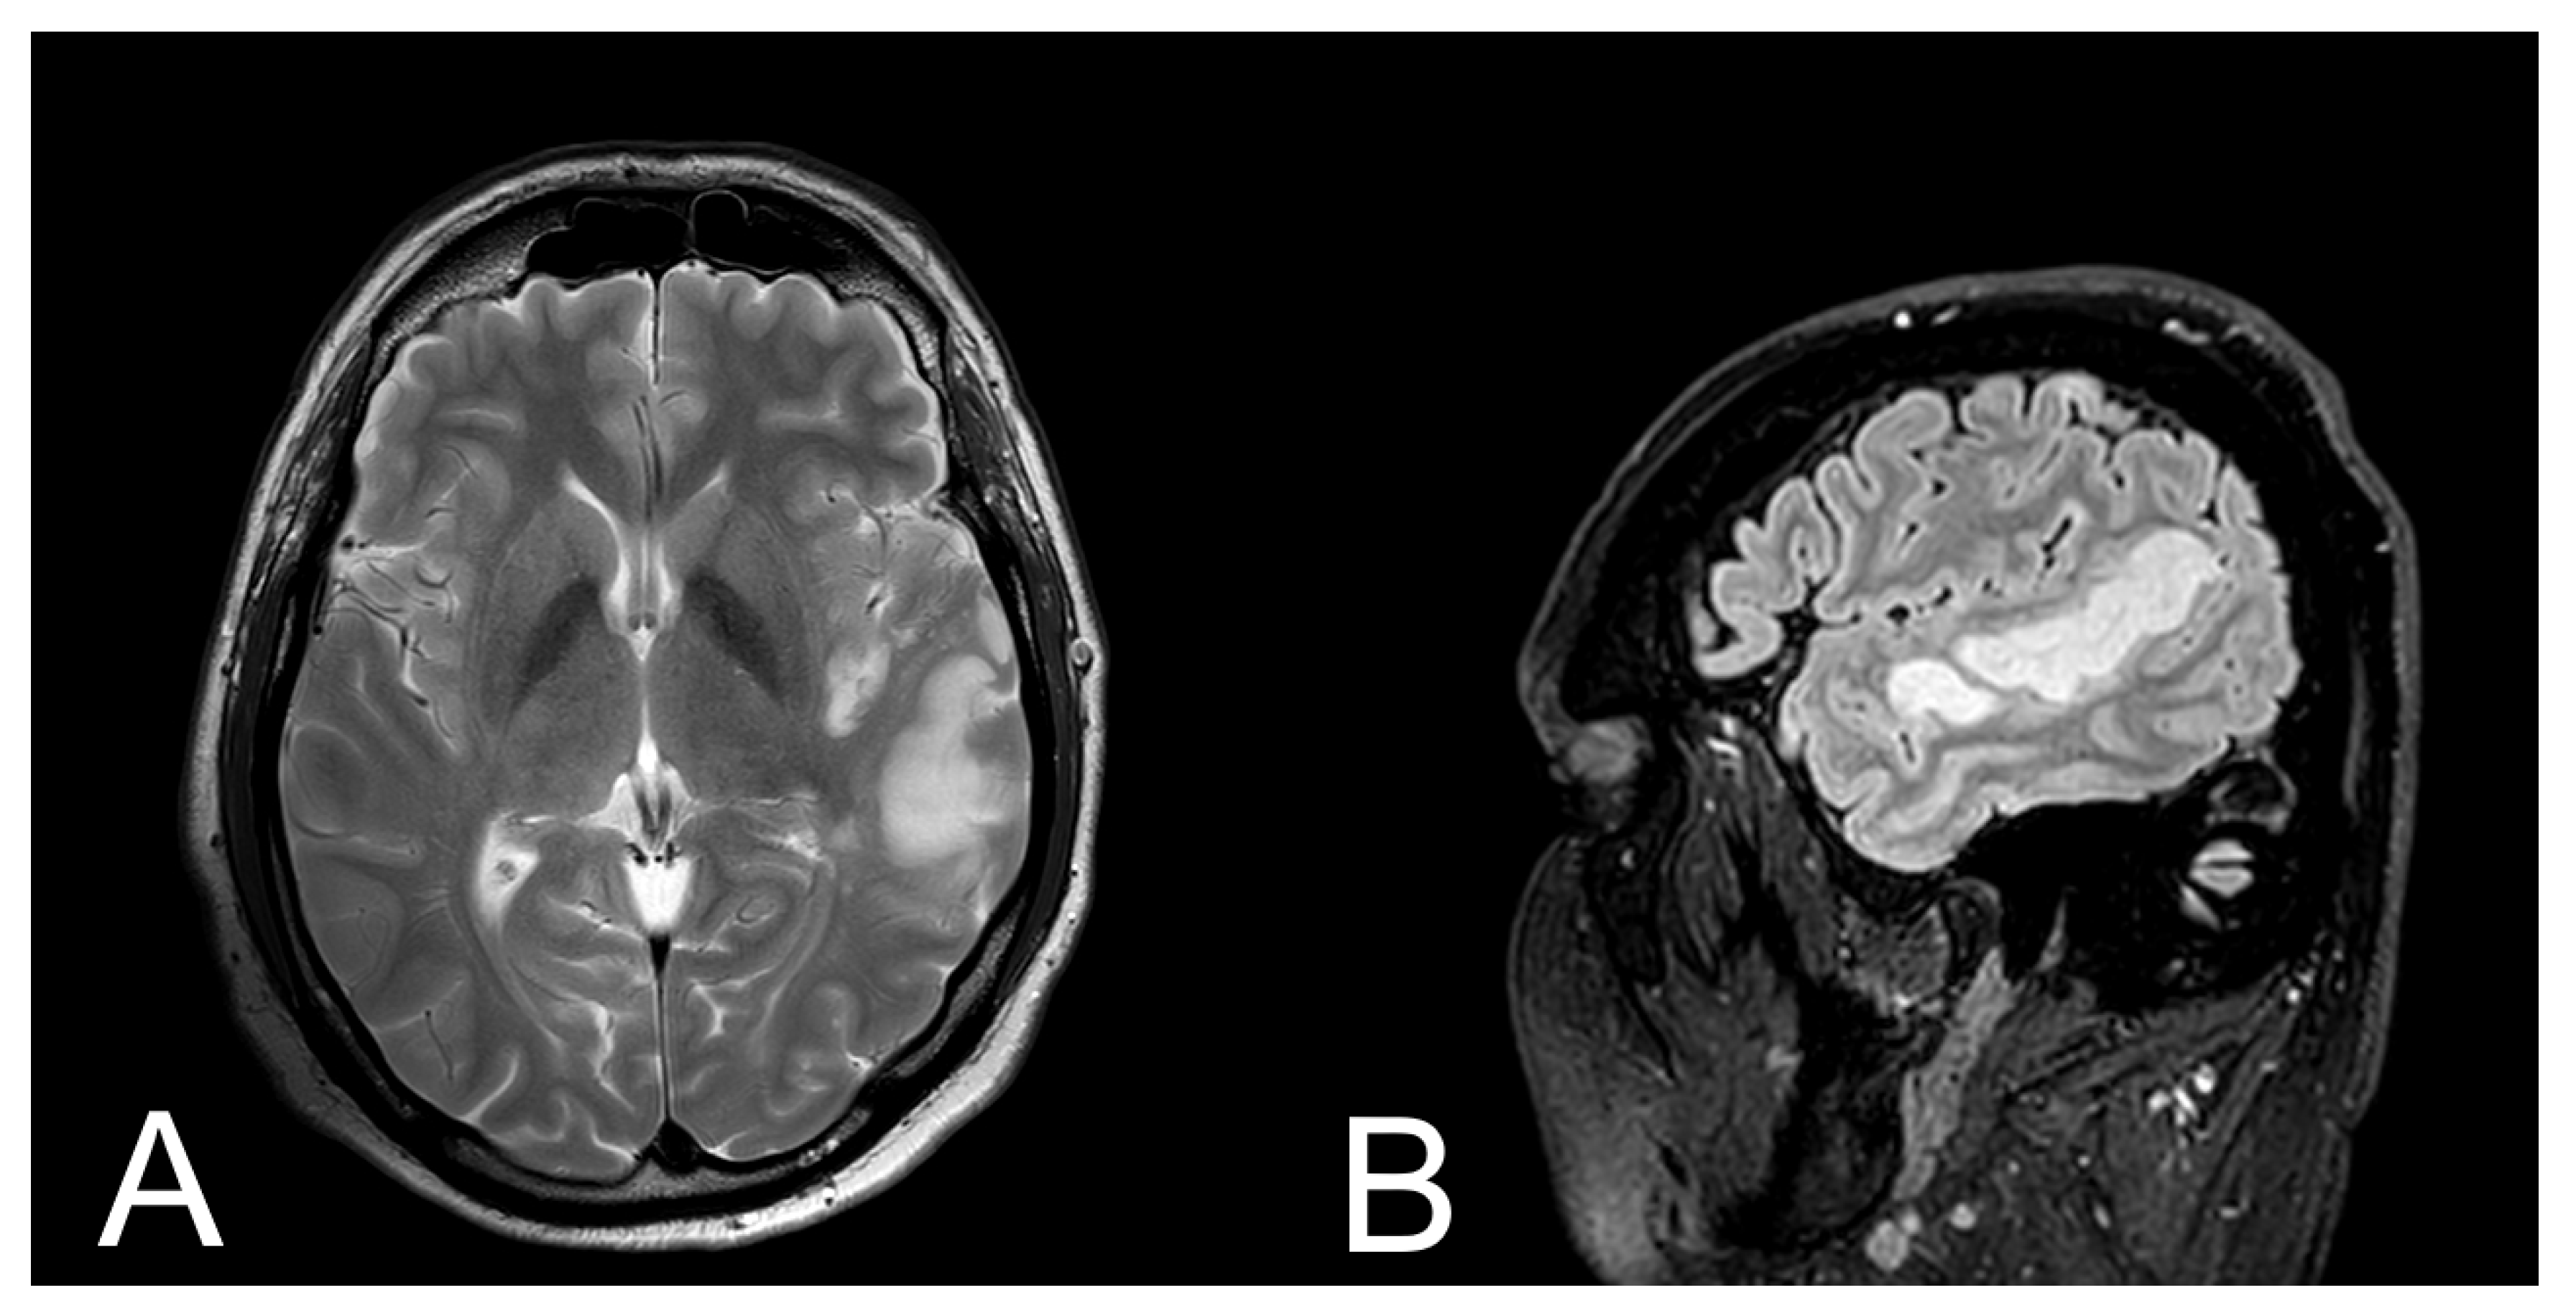

2. Case

2.1. Case History

2.5. MRI Protocol